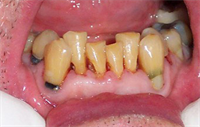

Dentaltown Learning Online- The Aesthetic Full Mouth Rehabilitation by Dr. John Nosti

Dentaltown Learning Online is proud to present John Nosti's latest extraordinary CE course...."The Aesthetic Full Mouth Rehabilitation" This course can be found here... Full Mouth Rehabilitations are one of the most difficult types of cases to handle in practice today. Many times these patients...  Read More